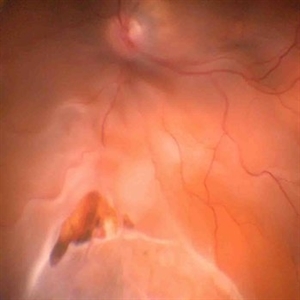

RPE rip in a case of Idiopathic polypoidal choroidopathy RPE rip in a case of Idiopathic polypoidal choroidopathyOct 23 2022 by Anjana Mirajkar, MS Ophthalmology OCT image in a of 61 year old male with RPE rip in a case of Idiopathic Polypoidal Choroidopathy. Photographer: Dr. Anjana Mirajkar -Retina Foundation, Ahmedabad Condition/keywords: Idiopathic polypoidal choroidopathy, RPE rip